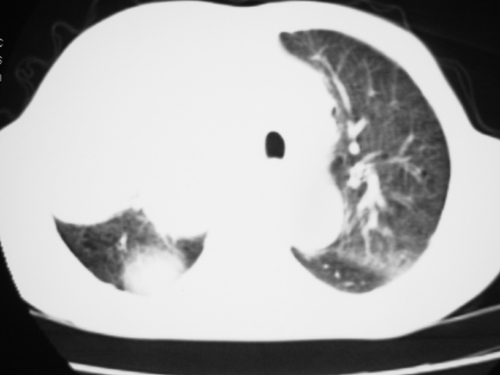

以下是引用yangyudong333在2008-4-29 5:46:00的发言:[br]1左上叶结节呈分叶状,边缘毛刺,考虑肺癌并纵隔淋巴结转移可能性大,结核待排,[br] [br]2右侧多发包裹性胸腔积液

以下是引用zsl6918在2008-4-29 9:15:00的发言:[br]右侧包裹性积液穿刺术后改变,肺内多发结节不除外转移可能。建议查胸水,问病史。